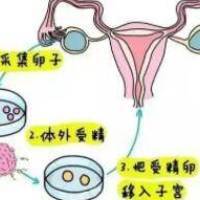

在多元家庭样子日益普及的即日,许多彩虹男女渴想通过人类辅助生殖技术达成生育梦想,却常常因为法律差异与跨国境医疗的复杂性而却步。台湾地区虽拥有亚洲优秀的生殖技术,但现行法规对彩虹男女的生育权仍存在显著程度范围——虽然彩虹婚姻已合法化,《人工生殖法》却尚未认可其辅助生殖利益。这种法律与技术之间的断层,使得跨国境医疗成为一条充溢挑战但是又逃避的路径。

台湾《人工生殖法》明白规定,仅持有合法婚姻证明的"异性夫妻"可申请辅助生殖服务,而且要提供医学不孕验证。彩虹男女尽管已然做完婚姻登记,仍被消除在服务范围除外。

技术选择与适配策略

1. 基因检查筛选技术(PGT)的必要性

三代试管技术(PGT-A/PGT-M)可筛查200+种遗传性疾病,将染色体不同寻常检出率提升至99.5%。建议有家属遗传性疾病史的伴侣首先选择支持该技术的机构,降低后代健康风险。

2. 冷冻技术的使用

玻璃化冷冻技术使用卵子/胚胎冻结生存率达96%以上,为跨境治疗提供时间弹性。建议尽早完毕取卵/男性生殖细胞体冷冻,避免频繁往复。